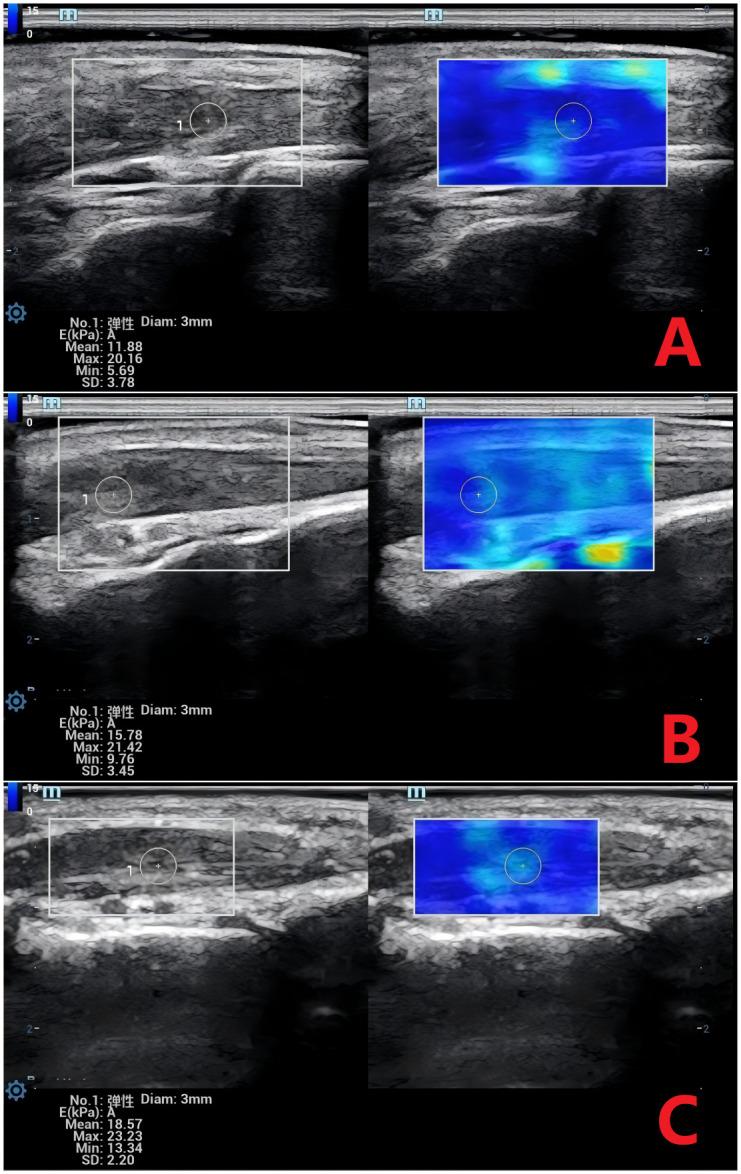

Emean increased progressively across groups (control: 11.88 kPa; T2DM: 15.78 kPa; T2DM+MC: 18.57 kPa; P < 0.01). T2DM+MC exhibited prolonged ΔAT (89.5 s vs. 50.5 s in controls) and reduced ΔPI (5.0 dB vs. 7.0 dB; P < 0.01). ROC analysis demonstrated high diagnostic accuracy for ΔAT (AUC = 0.970), Emean (AUC = 0.947), and ΔPI (AUC = 0.931) in detecting MC. Both SWE and CEUS showed excellent reproducibility (ICC > 0.80).

Emean在各组中逐渐升高(对照组:11.88 kPa;T2DM组:15.78 kPa;T2DM + MC组:18.57 kPa;P < 0.01)。T2DM + MC组表现出ΔAT延长(89.5秒,而对照组为50.5秒)和ΔPI降低(5.0 dB对7.0 dB;P < 0.01)。ROC分析表明,ΔAT(AUC = 0.970)、Emean(AUC = 0.947)和ΔPI(AUC = 0.931)在检测MC方面具有较高的诊断准确性。SWE和CEUS均显示出出色的可重复性(ICC > 0.80)。